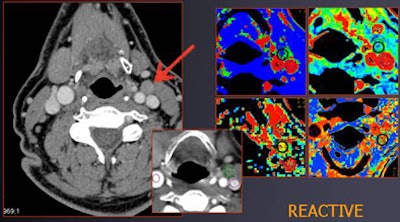

| A patient with tongue cancer had a known right-sided malignancy and a suspect node at left side. Normal rBV (2.7) and rBF (55) values suggest a reactive condition; histologic analysis confirmed the benignity of the node (MTT = 6.2, PS = 14). |